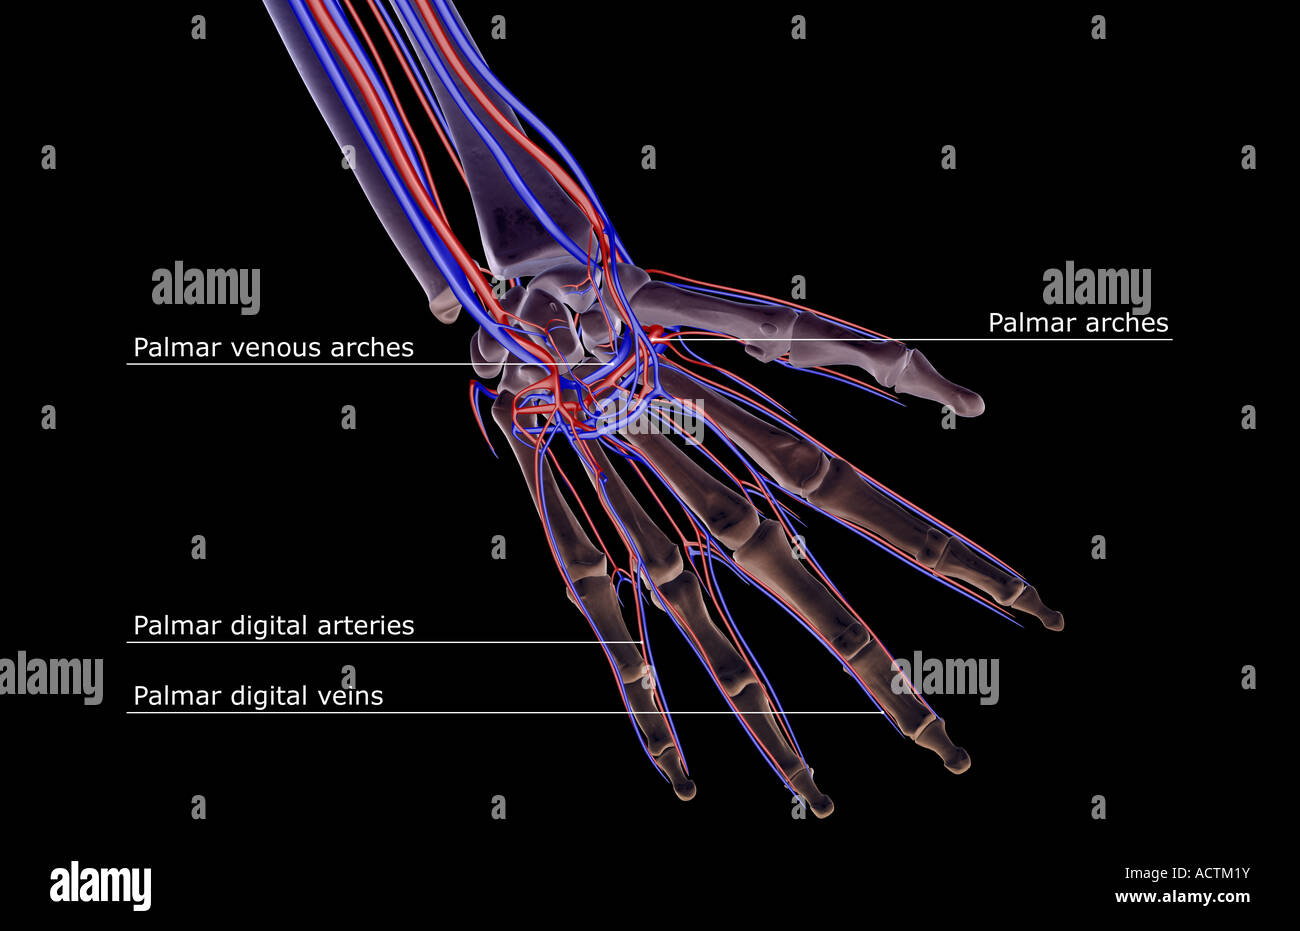

Blood supply of the forearm and hand Stock Photohttps://www.alamy.com/image-license-details/?v=1https://www.alamy.com/stock-photo-blood-supply-of-the-forearm-and-hand-13228118.html

Blood supply of the forearm and hand Stock Photohttps://www.alamy.com/image-license-details/?v=1https://www.alamy.com/stock-photo-blood-supply-of-the-forearm-and-hand-13228118.htmlRFACTM1Y–Blood supply of the forearm and hand